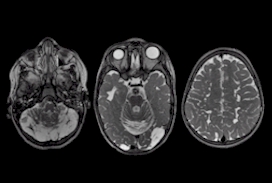

2023 London Imaging Discovery Day